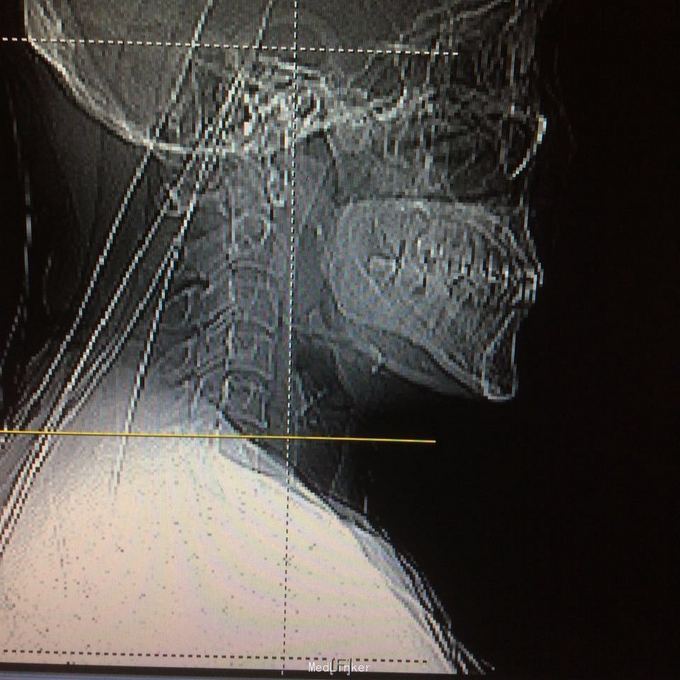

压头及右侧臂丛牵拉试验阳性,无明显浅感觉减退,右上肢肱三头肌肌力2级,双上肢腱反射活跃,双上肢病理征阳性 颈椎ct见颈椎6、7水平后纵韧带骨化,继发相应的椎管水平狭窄,自带核磁见颈椎2-7间盘向后突出,硬膜囊前缘受压